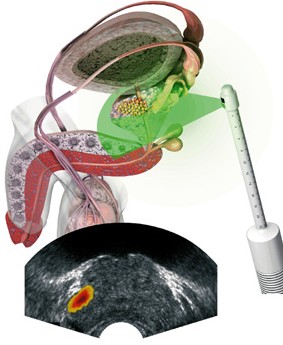

Лазерное воздействие

В последние годы широкое применение получило лечение хронического простатита лазерным излучением. Чаще всего используется низкоинтенсивное инфракрасное лазерное облучение, которое обладает высокой проникающей способностью и позволяет облучать простату как через кожу промежности, так и через стенку прямой кишки. Лазерная терапия малой интенсивности не вызывает побочных эффектов, мобилизует защитные силы организма, оказывает обезболивающее и стимулирующее действие. Лазерное излучение активизирует химические реакции, способствующие повышению уровня тканевого обмена.

В последние годы широкое применение получило лечение хронического простатита лазерным излучением. Чаще всего используется низкоинтенсивное инфракрасное лазерное облучение, которое обладает высокой проникающей способностью и позволяет облучать простату как через кожу промежности, так и через стенку прямой кишки. Лазерная терапия малой интенсивности не вызывает побочных эффектов, мобилизует защитные силы организма, оказывает обезболивающее и стимулирующее действие. Лазерное излучение активизирует химические реакции, способствующие повышению уровня тканевого обмена.

Низкоэнергетическое лазерное излучение

Отмечен выраженный терапевтический эффект воздействия низкоэнергетического лазерного излучения на железу с помощью специального лазерного ректального зонда со световодом. Назначение на область задней уретры полупроводникового лазера избавляет от применения таких неприятных для больного и травмирующих процедур, как тотальное промывание уретры, особенно бужирование семенного бугорка.